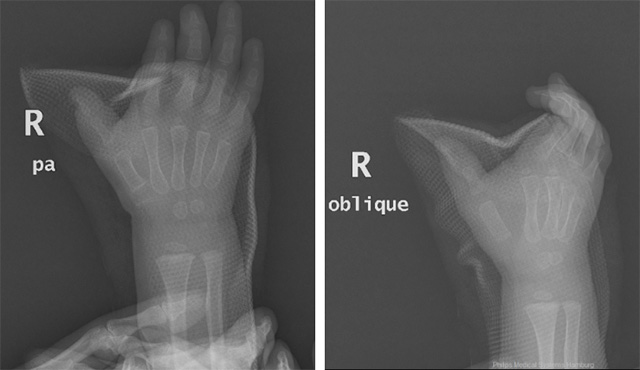

近期,玉溪市中醫(yī)醫(yī)院小兒骨科收治了兩名兒童蟹鉗樣復(fù)拇畸形的患兒。患兒分別為14個(gè)月大和20個(gè)月大,入院后小兒骨科針對(duì)患兒病情及時(shí)召開病歷討論專題會(huì),經(jīng)分析患兒相關(guān)查體及影象學(xué)檢查后考慮兩位患者分別為:先天性蟹鉗樣復(fù)拇畸形Wassel Ⅳ型和Ⅵ型 。

下圖為患兒2的術(shù)前手外觀及影像學(xué)資料